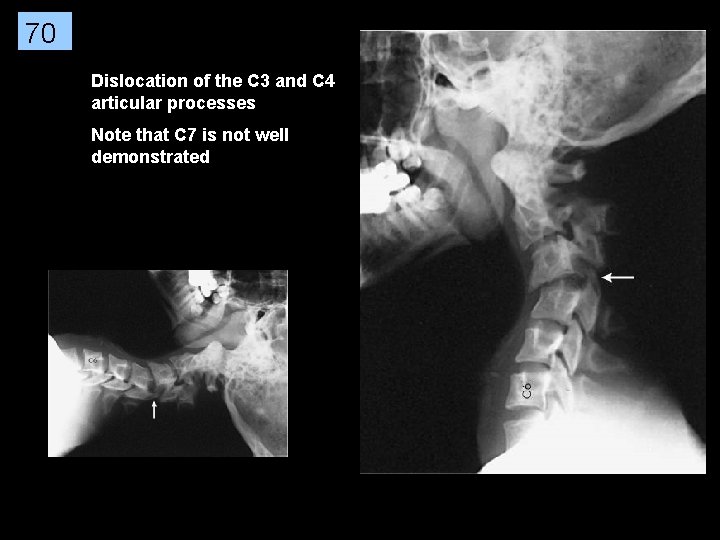

70 Dislocation of the C 3 and C 4 articular processes Note that C 7 is not well demonstrated